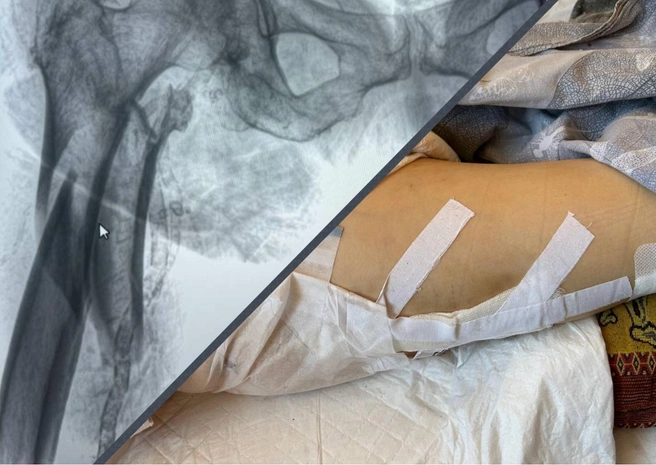

Диагноз, поставленный в самарской ГБ № 10: «Оскольчатый перелом диафиза бедренной кости». Внучка пенсионерки Евгения в разговоре с корреспондентом 63.RU уточнила, что травма оказалась чрезвычайно тяжелой.

«Кость была раздроблена как вилка и торчала в артерию. Врачи почти двое суток не решались на операцию, боялись, что она не перенесет. Как нам объясняли, бабушка могла скончаться прямо на операционном столе», — рассказывает Евгения.

Два дня 75-летняя женщина с невыносимой болью провела на вытяжке. Операцию в итоге сделали, но через несколько дней начались осложнения. А 14 сентября (это было воскресенье) Лидии Ивановне резко стало плохо. При этом жаловалась она еще и на сердце.